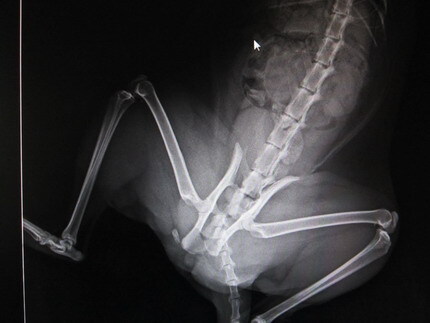

已完成醫助款案例 |